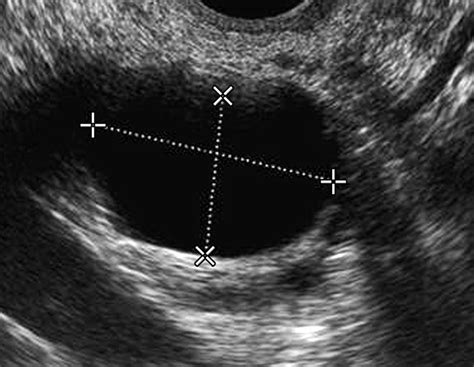

• Transvaginal Ultrasound (TVUS): This is generally considered the gold standard for examining the ovaries. A slim, wand-like transducer is inserted into the vagina, placing it in closer proximity to the ovaries. This method offers much higher resolution, allowing doctors to identify subtle changes in ovarian tissue.

After the procedure, the images are analyzed, and a report is generated. You might see terms like "simple cyst," "complex mass," or an IOTA (International Ovarian Tumor Analysis) score. A simple cyst is usually a fluid-filled sac that is common and often harmless, while a "complex" mass refers to an area that contains both solid and fluid elements, requiring follow-up.